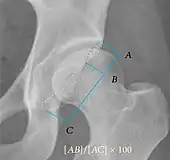

| Tönnis angle | ![]() |

Slope of the sourcil (the sclerotic weight-bearing portion of the acetabulum) | 0 to 10°

|

| Caput-sourcil angle[21] | ![]() |

Superior to the Tönnis angle in cases without joint space narrowing or subluxation.[21] The medial point of the sourcil is at the same height as the most superior point of caput femoris. | −6 to 12°[21]